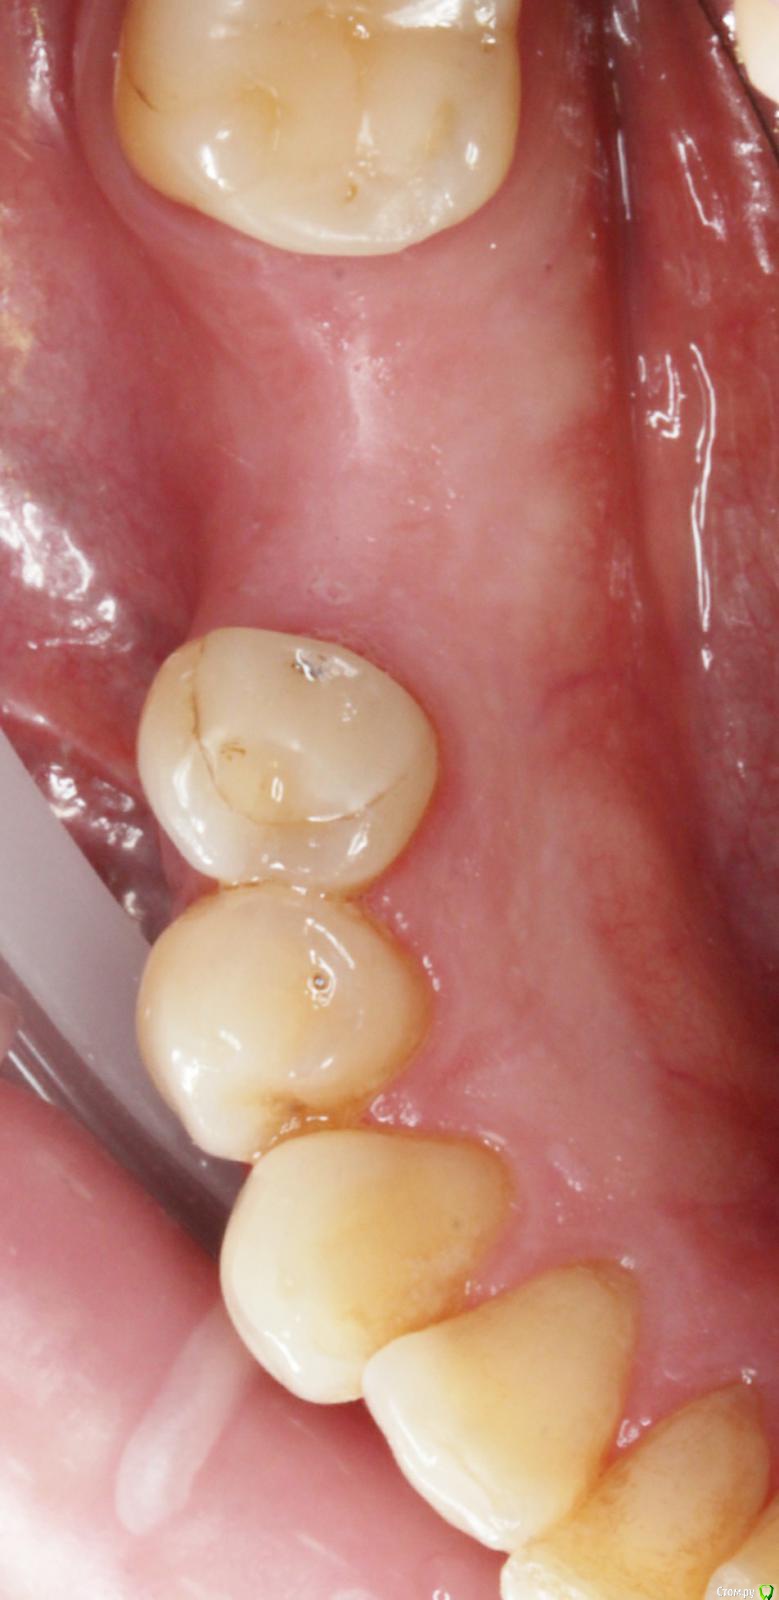

Dmitry DK Опубликовано 29 августа, 2019 Поделиться Опубликовано 29 августа, 2019 Добрый день всем! Случай достаточно заурядный, но возможно кому-то будет интересно. Результат - 2 года спустя 13 Ссылка на комментарий